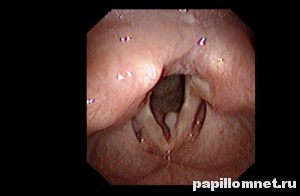

Снимок полипов, расположенных в горле человека

Полип выглядит как образование красного цвета. Он легко различим благодаря четким краям, ограничивающим полип от окружающих тканей, а располагается на тонкой ножке или на толстом основании. Его поверхность бывает как дольчатого, так и гладкого и ровного строения. Размеры разнятся, их количество тоже: они могут располагаться одиночно или парами, находясь друг напротив друга. Излюбленное место их локализации – середина голосовой связки.